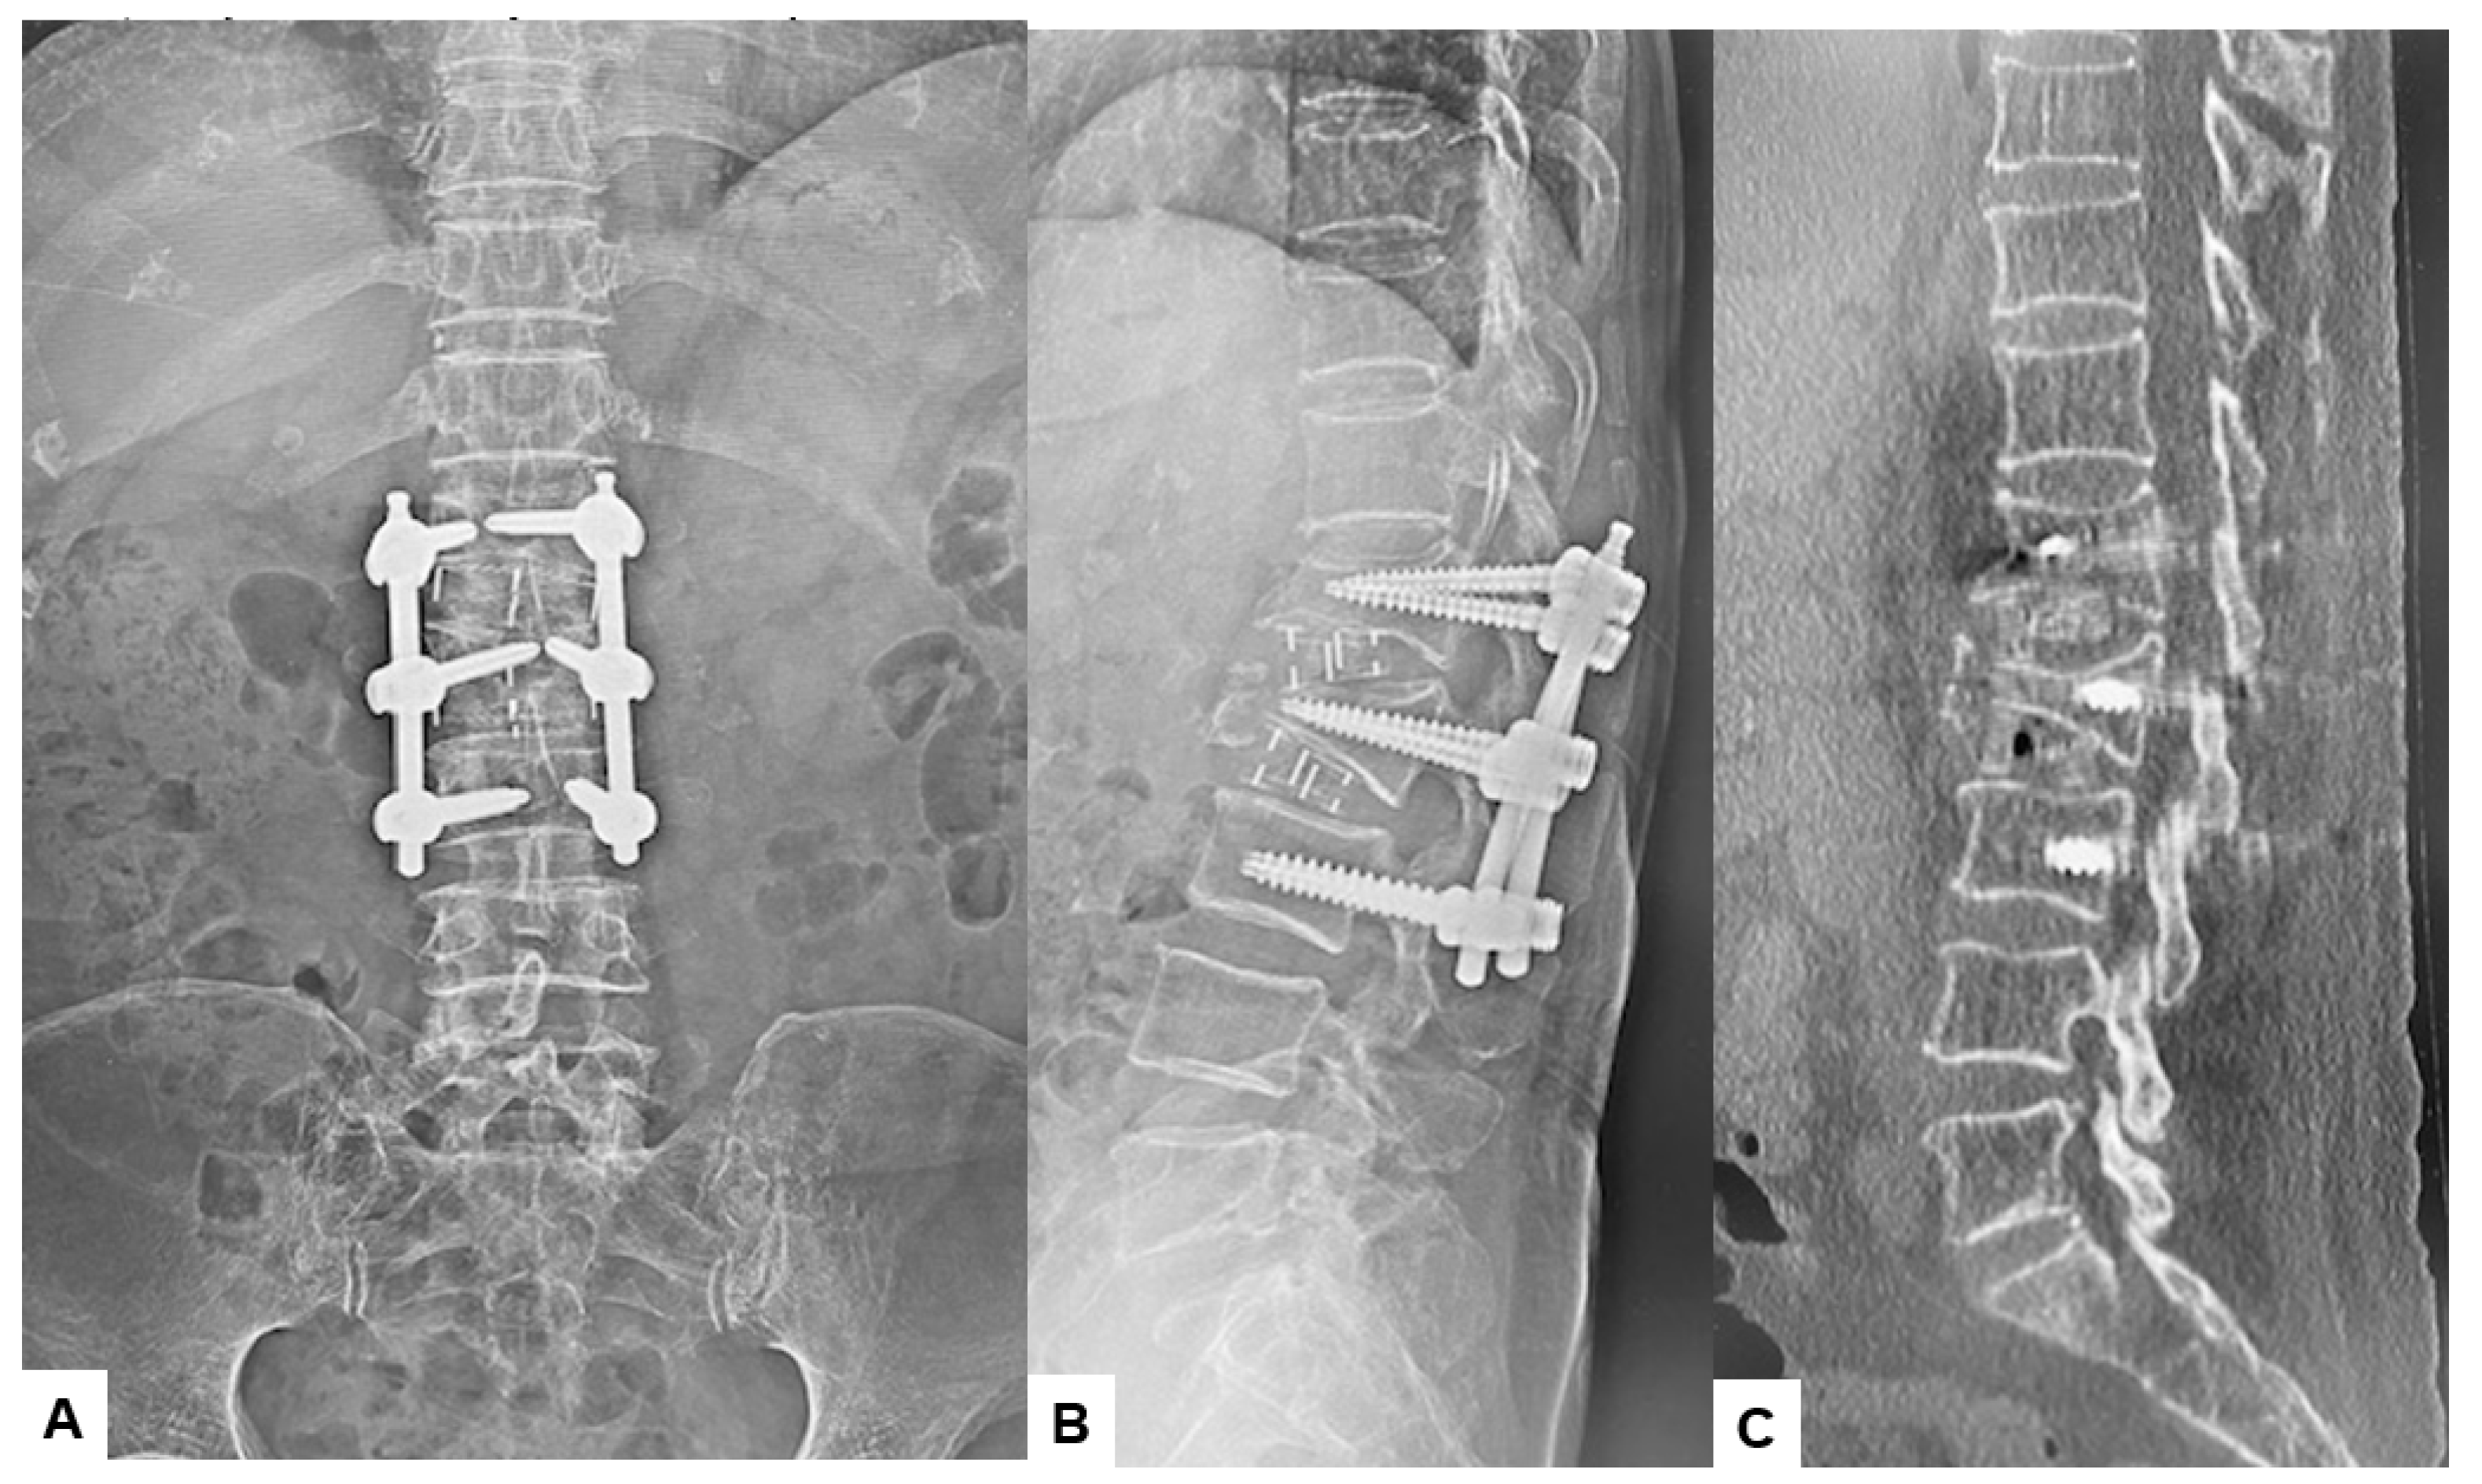

2.5. Postoperative Imagings